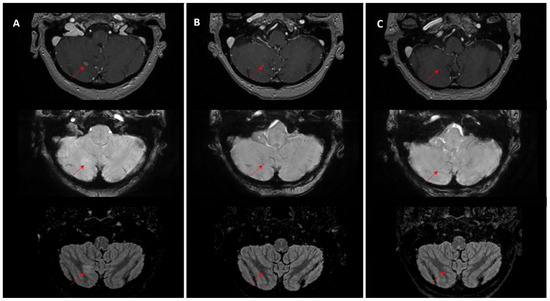

Temporal Dynamics and Heterogeneity in Brain Metastases: A Single-Center Retrospective Analysis of Vulnerabilities in Current MRI Surveillance Practices

by Claudia Tocilă-Mătășel, Sorin Marian Dudea and Gheorghe Iana

Medicina 2026, 62(1), 187; https://doi.org/10.3390/medicina62010187 (registering DOI) - 16 Jan 2026

Background and Objectives: Brain metastases frequently evolve over time in multiple waves, especially in patients with prolonged survival. Despite repeated imaging and targeted therapies, lesion-level continuity is fragmented in clinical practice, as follow-up is typically limited to pairwise MRI comparisons. The aim of the study is to assess the ability of routine narrative MRI follow-up reports to preserve longitudinal lesion identity and to reconstruct a coherent trajectory of disease evolution. Materials and Methods: We conducted a single-center, retrospective, observational study of all brain MRI examinations performed between June 2024 and June 2025 (n = 731 scans, 616 patients). All imaging reviews and longitudinal lesion tracking were performed by one board-certified neuroradiologist. Adult patients with confirmed brain metastases and at least three MRI examinations (including external studies) were included. We assessed the concordance of routine narrative MRI follow-up reports against a longitudinal review of all available MRIs and treatment timelines, which served as the reference standard. Lesion identity was considered preserved when reports explicitly recognized and linked lesions across time points, and lost when identity was omitted or ambiguous in at least one report. Results: The final cohort comprised 73 patients (477 tracked lesions). More than half of monitored lesions disappeared (42.9%) or evolved into post-treatment sequelae (9.9%), and were omitted from narrative reports, limiting retrospective recognition without prior imaging. The ability of routine reports to preserve lesion identity declined as cases became more complex. Concordance was higher in uniform evolution patterns (≈60%) but dropped to 18.2% in mixed evolution. A similar decline was seen with sequential metastatic waves, defined as new metastases appearing at distinct time points: 65.2% (1 wave), 46.7% (2 waves), 18.2% (3 waves), and complete loss of continuity when >3 waves occurred. Conclusions: Routine narrative MRI follow-up reports generally provide adequate information in simple cases with uniform lesion behavior, but tend to lose critical details as disease trajectories become more complex, particularly in heterogeneous or multi-wave disease. Even when individual lesions are identified across examinations, documentation remains fragmented and reflects only a snapshot of the disease course rather than an integrated longitudinal perspective. These findings highlight a critical vulnerability in current follow-up practices. Improving lesion-level continuity, potentially through AI-assisted tools, may enhance the accuracy, consistency, and clinical utility of MRI surveillance in patients with brain metastases. Full article

Figure 1